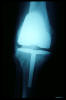

Prótesis completa de rodilla. Situación postquirúrgica.

Prótesis completa de rodilla. Situación postquirúrgica. Lateral.

Prótesis completa de rodilla.Lateral.

Prótesis completa de rodilla. Frontal.